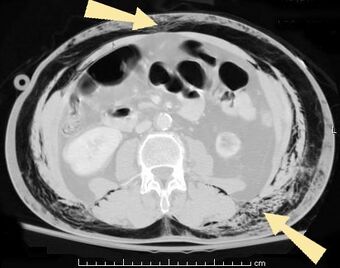

An abdominal CT scan of a patient with subcutaneous emphysema (arrows)

Significant cases of subcutaneous emphysema are easy to diagnose because of the characteristic signs of the condition.[1] In some cases, the signs are subtle, making diagnosis more difficult.[13] Medical imaging is used to diagnose the condition or confirm a diagnosis made using clinical signs. On a chest radiograph, subcutaneous emphysema may be seen as radiolucent striations in the pattern expected from the pectoralis major muscle group. Air in the subcutaneous tissues may interfere with radiography of the chest, potentially obscuring serious conditions such as pneumothorax.[18] It can also reduce the effectiveness of chest ultrasound.[27] On the other hand, since subcutaneous emphysema may become apparent in chest X-rays before a pneumothorax does, its presence may be used to infer that of the latter injury.[13] Subcutaneous emphysema can also be seen in CT scans, with the air pockets appearing as dark areas. CT scanning is so sensitive that it commonly makes it possible to find the exact spot from which air is entering the soft tissues.[13] In 1944, M.T. Macklin and C.C. Macklin published further insights into the pathophysiology of spontaneous Macklin's Syndrome occurring as a result of a severe asthmatic attack.